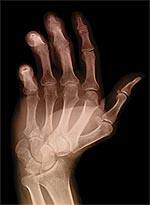

Bone Osteocalcin Regulates Energy Metabolism | |

A new study published in the scientific journal Cell is the first to establish a relationship between the vitamin K-dependent hormone, osteocalcin, and regulation of insulin.* The findings establish the skeleton as an endocrine organ that controls energy metabolism, which has important implications for the treatment of obesity and diabetes. Using genetically altered mice, investigators determined that osteocalcin, a hormone secreted by osteoblasts (a type of bone cell), is capable of stimulating insulin secretion and improving insulin sensitivity. The findings indicate that the skeleton helps regulate energy metabolism in a feedback-loop fashion. “Our results add further credence to the concept that bone and energy metabolisms exert reciprocal regulations,” wrote the authors. “By revealing that the skeleton exerts an endocrine regulation of sugar homeostasis this study expands the biological importance of this organ and our understanding of energy metabolism,” they concluded. —Dale Kiefer | |

| *Lee NK, Sowa H, Hinoi E, et al. Endocrine regulation of energy metabolism by the skeleton. Cell. 2007 Aug 10;130(3):456-69. | |